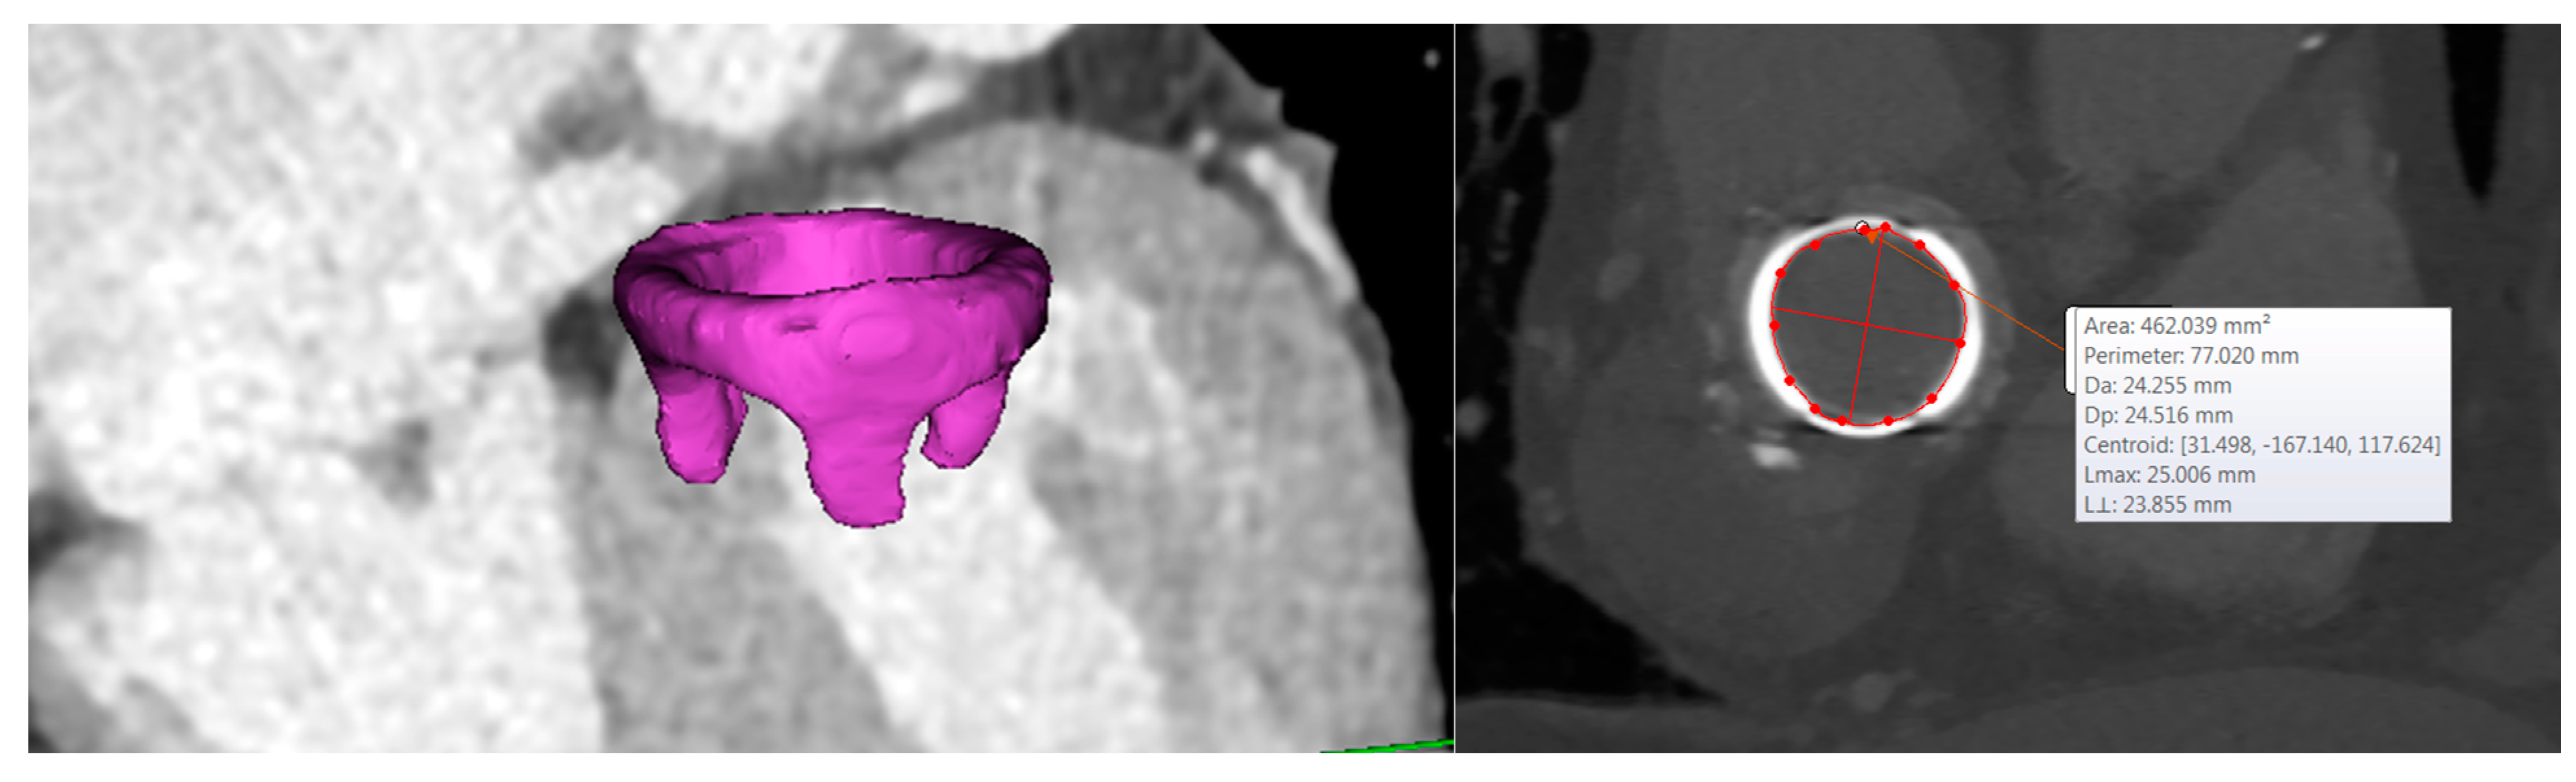

Figure 2.

3D segmentation of the bioprosthetic heart valve and dimension of the mitral valve annulus.

The geometrical model of THV was acquired with a high-resolution micro-CT scanner as described in our previous study [15]. The computer-aided-design model (CAD) of THV was imported as STL file in Mimics, and the THV was then positioned. The framework of basic steps of CAD modeling for neo-LVOT quantification is based on the approach developed by Blanke and collaborators [6]. These consisted of the segmentation of the mitral annulus, an assessment of the mitral trajectory, the virtual positioning of THV, the generation of the neo-LVOT centerline, and the quantification of neo-LVOT area.